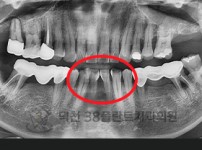

치료전후